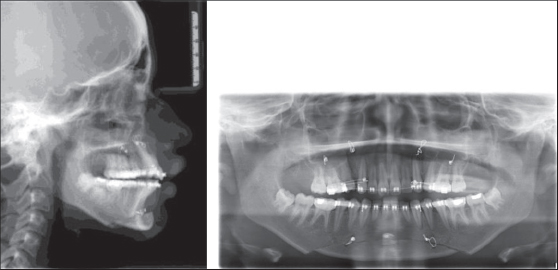

Figure 3: Preoperative lateral cephalogram and orthopantamogram-group I

thumb

Figure 4: 1-week postoperative lateral cephalogram and orthopantamogram- Group I

Figure 5: 6-month postoperative lateral cephalogram and orthopantamogram- Group I